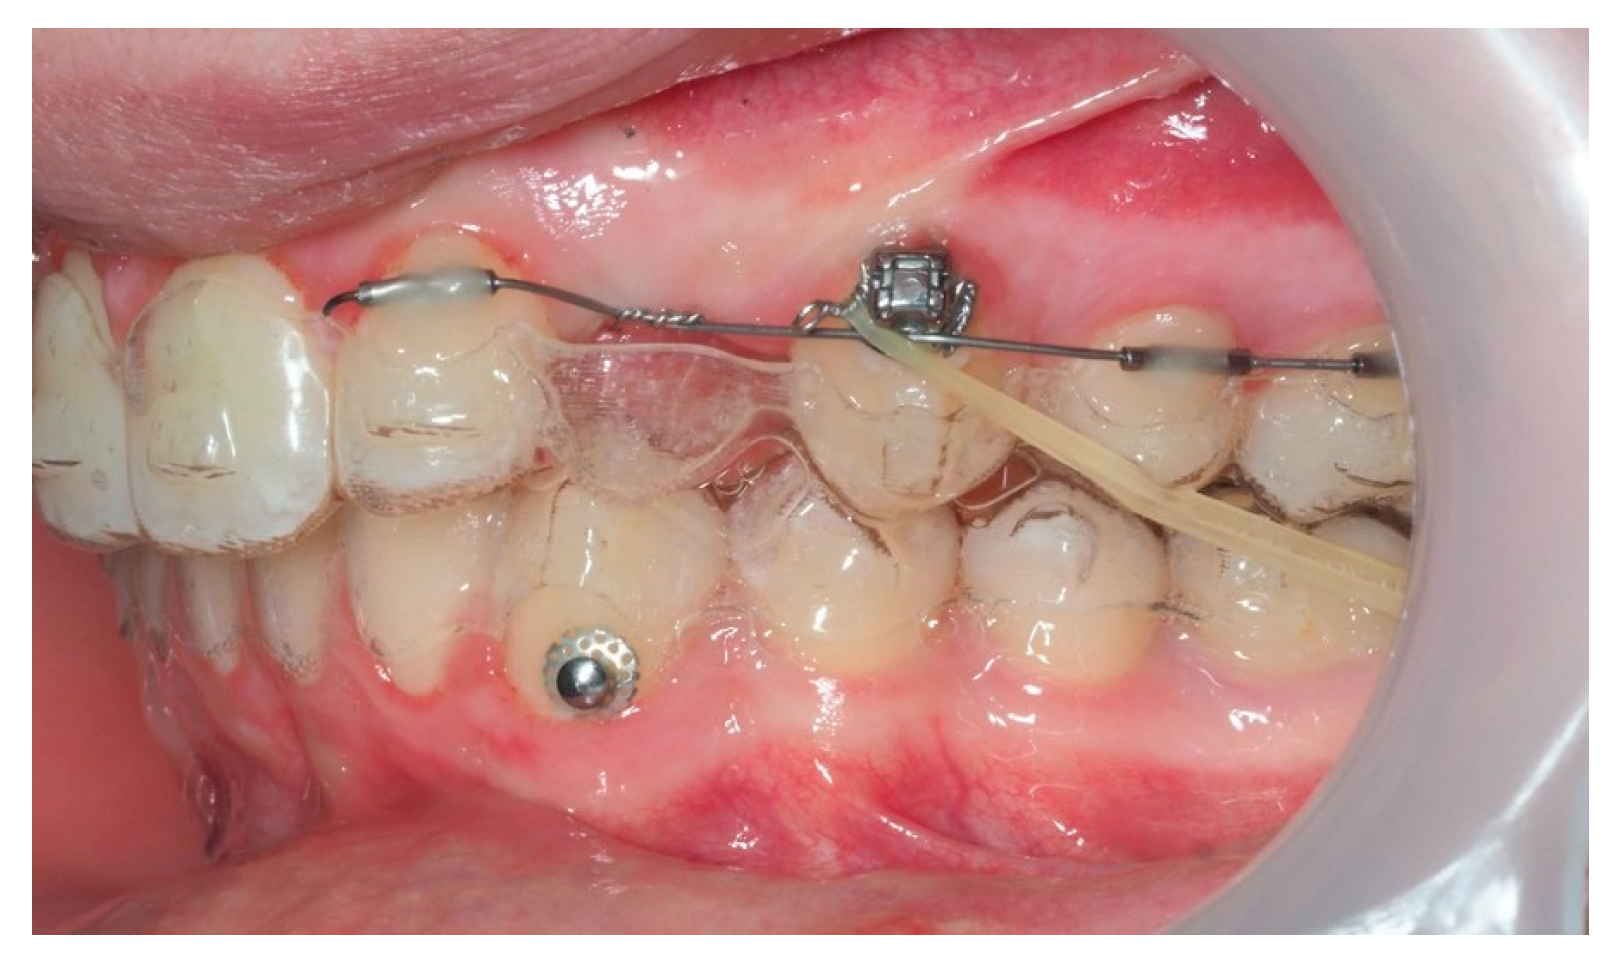

Approximately 7 months later, a palatal mini-implant was placed between teeth 24 and 25, serving as stable anchorage for distal traction using an elastic chain, which was replaced monthly (Figure 15). This movement positioned the canine away from the lateral incisor root. Aligners were customized and adjusted throughout treatment.

Figure 15.

Adjusted aligners, palatal mini-implant, and elastic chain used for distalizing the canine; 7 months after the surgery.

Following initial distalization, a sectional fixed appliance was bonded from tooth 11 to 26. On tooth 24, a bracket with a metallic ligature was used to support Class II elastics. Mini-tubes were bonded on teeth 22, 25, and 26, and the aligners were trimmed accordingly (Figure 16). A ligature wire connected the palatal button on the canine to a 0.014” nitinol archwire (Figure 17).

Figure 16.

Sectional fixed appliance from teeth 11 to 26, with support for Class II elastics to improve sagittal relationship; 14 months after the surgery.